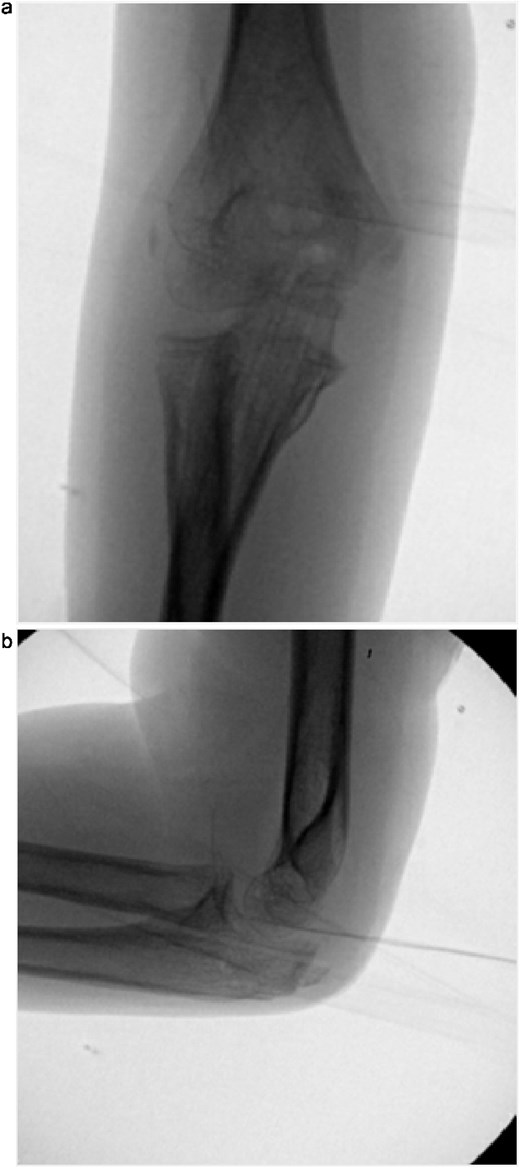

Initial radiographs following closed reduction and casting demonstrated fractures of the proximal ulna and radial neck, with improved alignment but limited bony detail (Fig. 1a and b). Elbow effusion was also noted. A CT scan performed 3 days later showed 18° apex-medial angulation of the radial neck fracture, slight inferior subluxation of the radial head, and linear calcification near the ulnotrochlear interval, concerning for an intra-articular fragment (Fig. 2).

(a, b) Initial radiographs after closed reduction, showing proximal ulna and radial neck fractures.